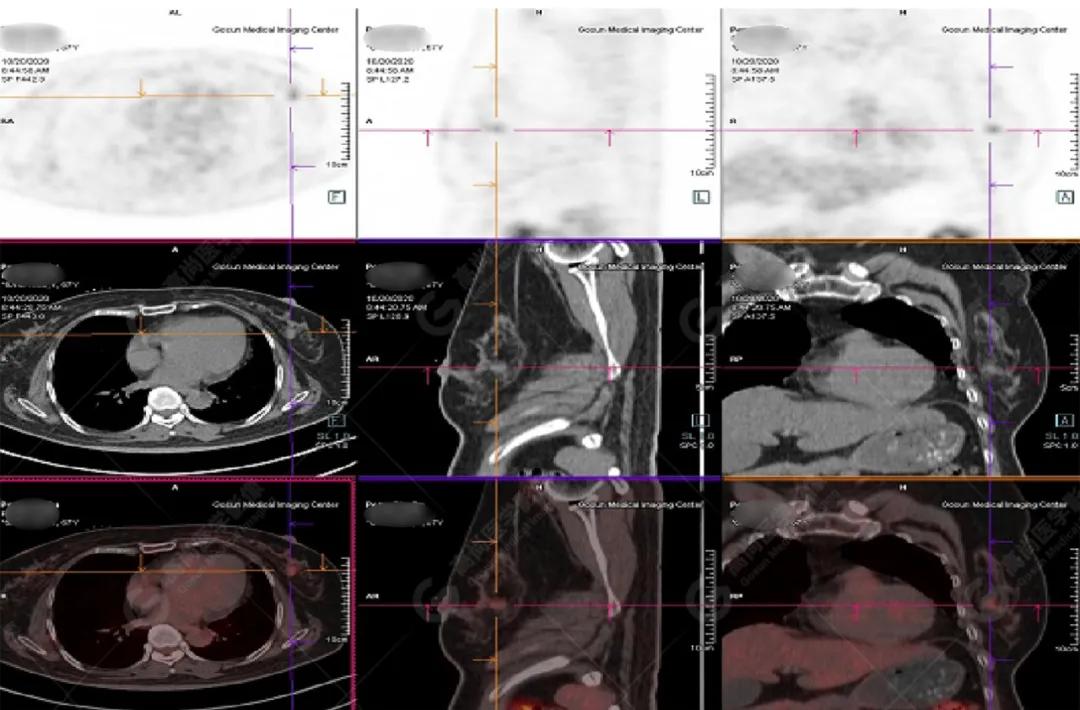

PET/CT

影像图

左胸一后肋溶骨性骨质破坏,周围伴软组织形成,FDG代谢增高,SUVmax为10.9。

找到引起骨痛病灶,病因:原发?转移?感染?

宫颈一片状稍低密度影,FDG结节样代谢增高,SUVmax为10.2。

最终诊断: 宫颈癌伴肋骨单发骨转移。